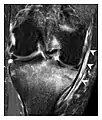

Fatigue fractures are more frequent in women which may be due to the relatively smaller bones of women. Moreover, pregnancy is a well-recognized risk factor for femoral neck fatigue fracture. While fibular and metatarsal fractures have a low risk of complications, other sites including the femoral neck, midanterior tibia, navicular, talar, and other intraarticular fractures are prone to complications such as delayed union, nonunion, and displacement. The site of the insufficiency fracture may be specific to the activity: for example, rugby and basketball players are more prone to navicular fractures, while gymnasts have a higher risk for talar fractures (Figure 7). Long distance runners are at increased risk for pelvic, tibial (Figures 8 and 9), and fibular fractures. In the military, calcaneus (Figure 10) and metatarsals are the most commonly cited injuries, especially in new recruits. Billiard players are at risk for upper limb fractures (Figure 11).[1]

Figure 7: Fatigue fracture of the talus in a 25-year-old male basketball player with right hind foot and ankle pain, without history of trauma, and a normal initial radiograph (not shown). (a) One-month followup lateral radiograph shows normal appearance. (b) Sagittal T1-weighted MRI shows an irregular fracture line (arrow) within an ill-defined area of hypointensity corresponding to bone marrow edema.[1]